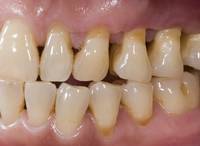

Zahnfleischschwund durch

Parodontitis: An allen Zähnen eines Kiefers -

hier am Oberkiefer - geht das Zahnfleisch

zurück, am Unterkiefer nicht.

Die empfindlichen Zahnhälse liegen nun zum

Teil frei und ungeschützt und sind

kariesgefährdet.